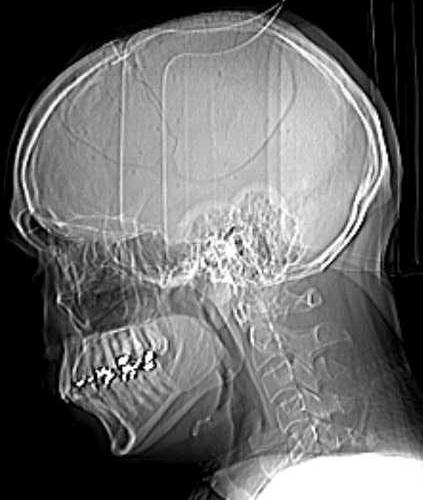

Und nun kann ich mir also mal genauer ansehen was Die mir damals aus dem Schädel gesägt hatten:

Haben die doch fein wieder eingesetzt

Ich kann zwar nur erahnen was ich da wirklich sehe aber zumindest das Schädelstück konnte ich identifizieren. Das gebrochene Schlüsselbein kann ich aber nirgends erkennen, da muss ich weiterhin dem Krankenbericht glauben

Ich habe damals wirklich verdammt viel Glück gehabt!